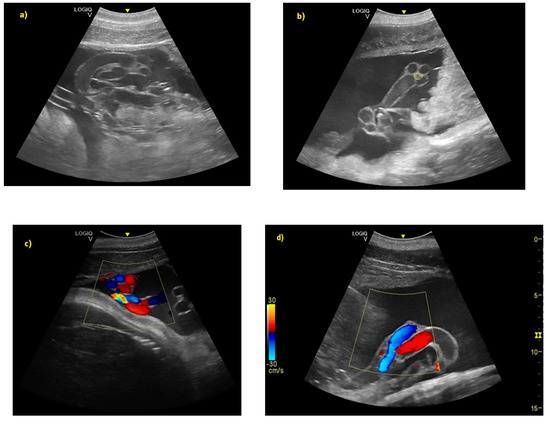

- Sklansky, M.; Renner, M.; Clough, P.; Levine, G.; Campbell, M.; Stone, R.; Schmitt, T.; Chang, R.K.; Shannon-Rodriguez, J. Fetal Echocardiographic Evaluation of the Bottlenose Dolphin (Tursiops truncatus). J. Zoo Wildl. Med. 2010, 41, 35–43. [Google Scholar] [CrossRef] [PubMed]

- Rychik, J.; Ayres, N.; Cuneo, B.; Gotteiner, N.; Hornberger, L.; Spevak, P.; Van der Veld, M. American Society of Echocardiography guidelines and standards for performance of the fetal echocardiogram. J. Am. Soc. Echocardiogr. 2004, 17, 803–810. [Google Scholar] [CrossRef] [PubMed]

- Makikallio, K.; Räsänen, J.; Mäkikallio, T.; Vuolteenaho, O.; Huhta, J.C. Human fetal cardiovascular profile score and neonatal outcome in intrauterine growth restriction Ultrasound. Obstet. Gynecol. 2008, 31, 48–54. [Google Scholar]

- Powell, J.; Archibald, R.; Cross, C.; Rotstein, D.; Soop, V.; McFee, W. Multiple congenital cardiac abnormalities in an Atlantic bottlenose dolphin (Tursiops truncatus). J. Wildl. Dis. 2009, 45, 839–842. [Google Scholar] [CrossRef]